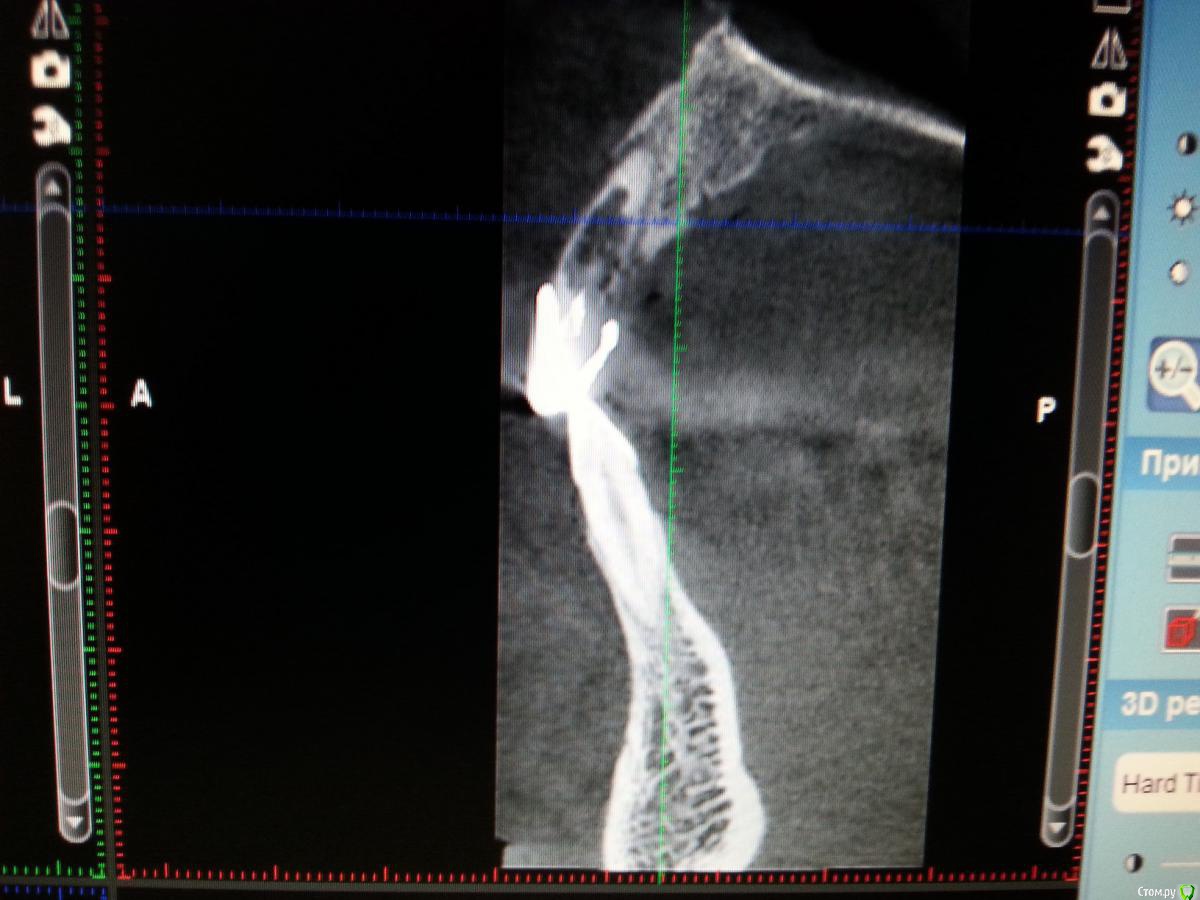

Zamber Опубликовано 29 декабря, 2016 Автор Поделиться Опубликовано 29 декабря, 2016 Сегодня показал врачу КТ. Одномоментная имплантация не грозит теперь точно, поскольку кость практически отсутствует. Выкладываю некоторые фрагменты, надеюсь на комментарии. Могут ли здесь быть шансы? Ссылка на комментарий

red_butler Опубликовано 30 декабря, 2016 Поделиться Опубликовано 30 декабря, 2016 Могут ли здесь быть шансы? Я бы вел отсрочено 1 Ссылка на комментарий

Zamber Опубликовано 30 декабря, 2016 Автор Поделиться Опубликовано 30 декабря, 2016 Я бы вел отсрочено Мне предложили костную пластику, а затем - в зависимости от результата. Это для 11 (тот, что на КТ). У 12 толщина кости 4,6, предлагают имплантировать. Толщины достаточно? Ссылка на комментарий